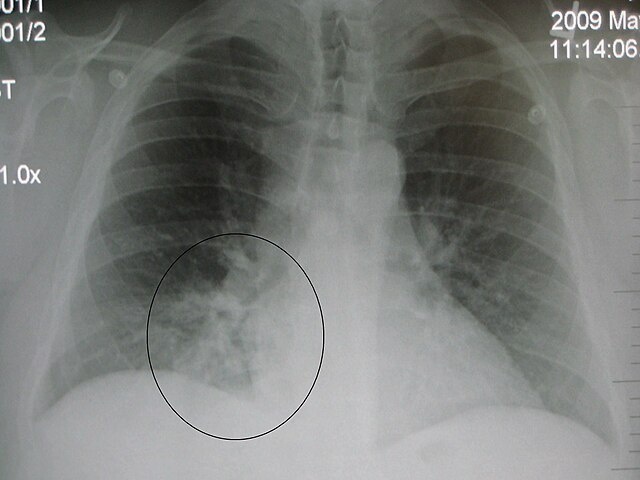

• Рентгенография органов грудной клетки

❗Изменения, которые мы видим на рентгенограмме проходят медленнее, чем клинические симптомы, поэтому если вы видите, что ребенок выздоровел, то нет необходимости делать рентген повторно, а если все-таки очень хочется, то сделайте через2-3 недели.